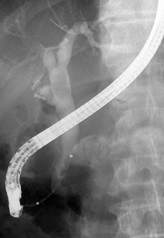

EPLBD

大きな総胆管結石を摘除するために行う、内視鏡的乳頭ラージバルーン拡張術